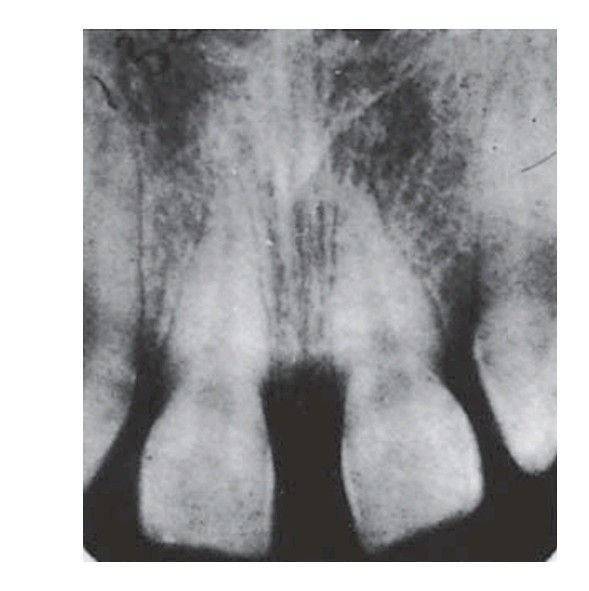

Missing lateral incisors

Congenital absence of lateral incisors with spacing of the anterior teeth.